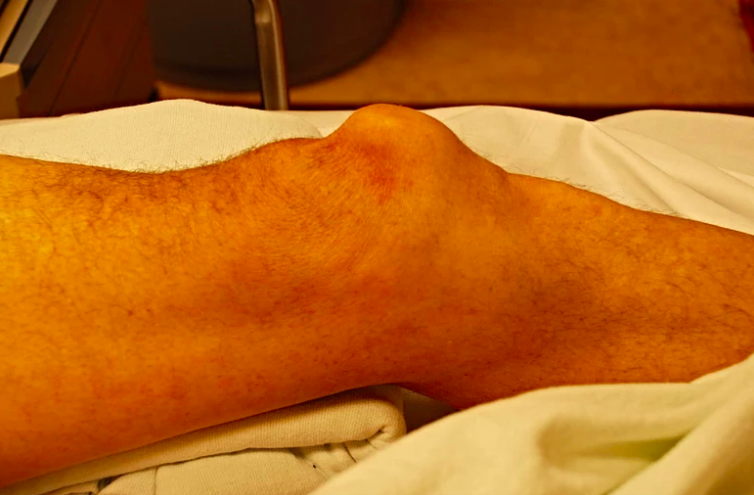

Pas. med fall på lett flektert kne. Bruker anabole steroider. Manglende ekstensjonsevne i kneet.

Hva tror du har skjedd her? Behandling?

Quadricepsseneruptur. Må teste for ekstensjonsevne. partielle skader med intakt ekstensjonsevne forekommer.